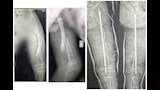

نجح فريق طبي بمستشفى سوهاج العام، في إجراء جراحة عظام كبرى لطفلة تبلغ من العمر 6 سنوات، مصابة بمرض العظام الزجاجية وكسر في عظمة الفخذ، وهي من العمليات الدقيقة والمعقدة؛ نظرًا لهشاشة العظام الشديدة التي يسببها المرض.

واستغرقت العملية نحو 3 ساعات، تضمنت إصلاح التشوهات بعظمة الفخذ وتثبيت الكسر باستخدام مسمار نخاعي متمدد ذاتي الإطالة، المخصص لحالات العظام الزجاجية.